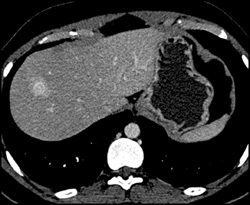

Diagnosis

Hemangioma